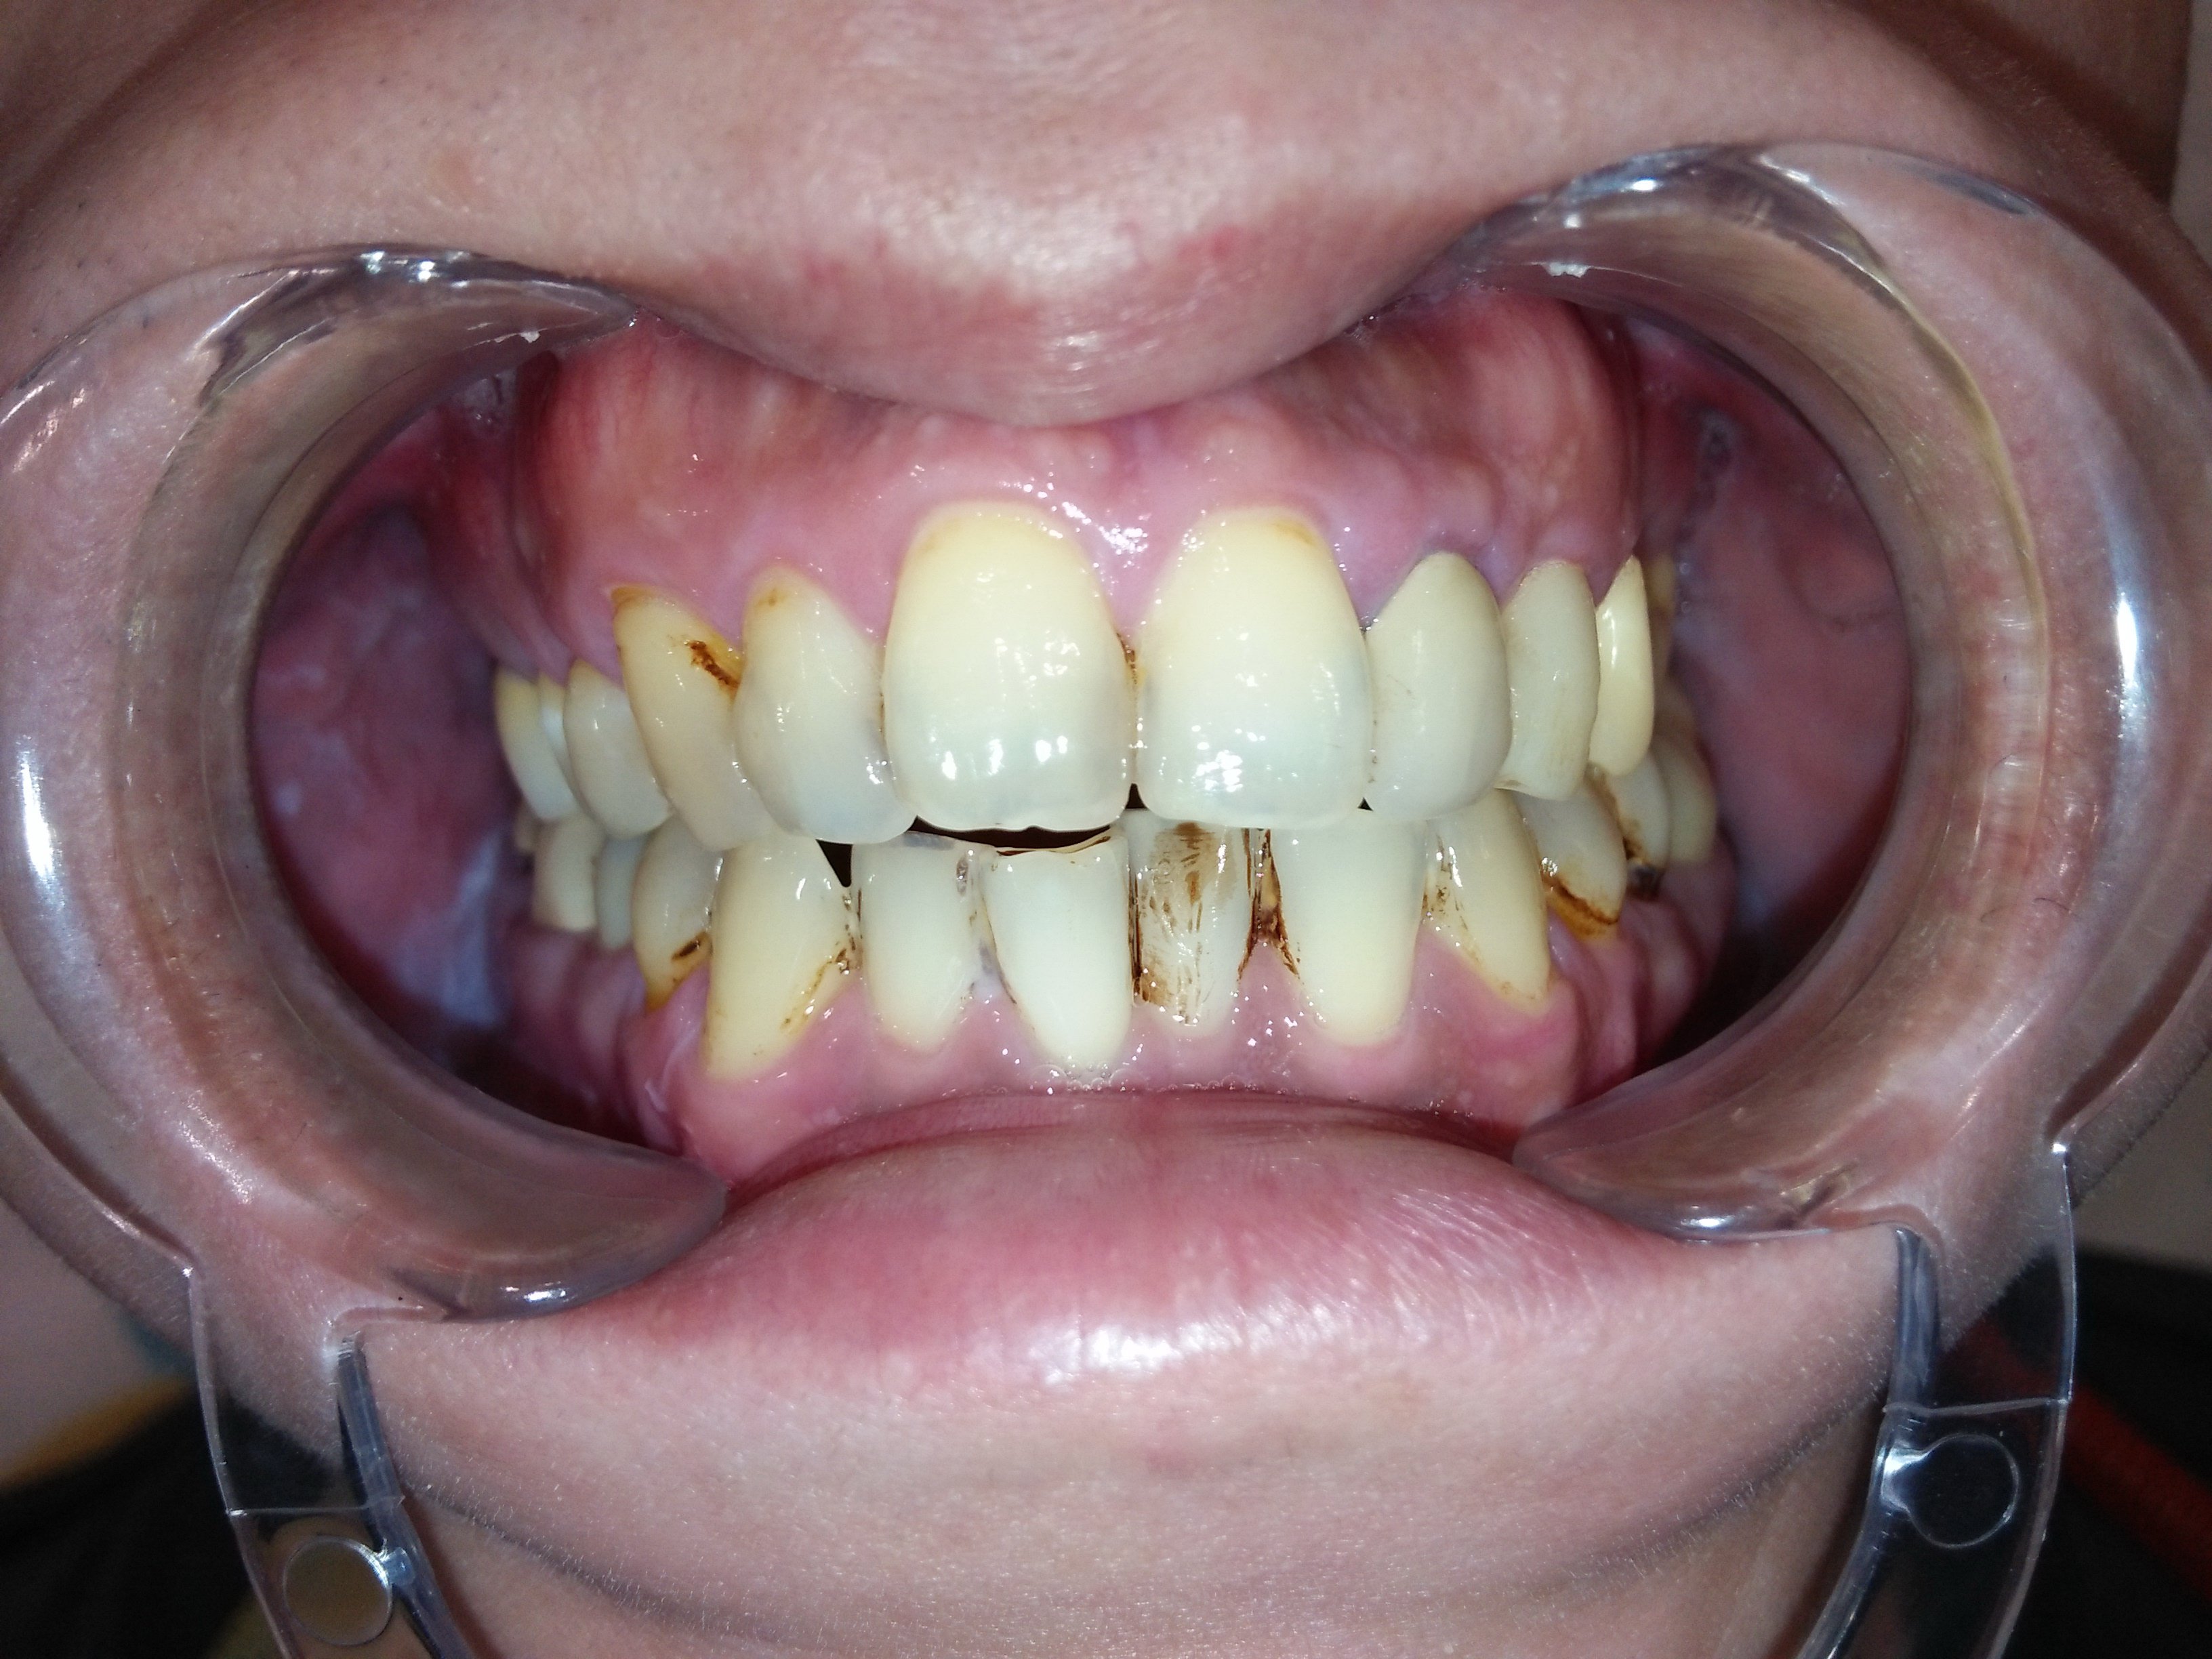

這才發現原來補骨醫師技術有別,不是有補就好,蛀牙也不是一再重複處理讓牙齒神經反覆受刺激;需要先處理咬合、排列的問題,再將缺牙、蛀牙和前牙美觀合併處理,不但解決了牙縫塞東西造成蛀牙不斷,也讓牙齒排列改變改變外觀。

改變排列及牙齒上下相對位置,才能讓咬合和受力分配較佳並穩定,不會產生牙縫遭受直接衝擊的問題。